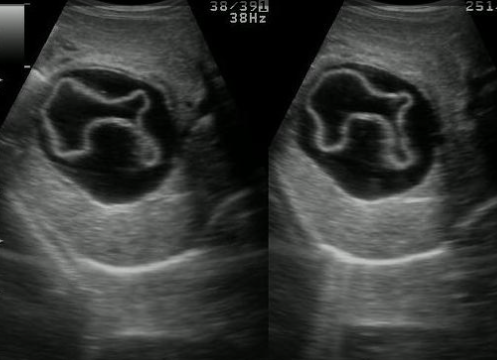

simple cyst ② polycystic liver disease (PLD)

상염색체 우성 다낭성 간질환이라고도 불리는 다낭성 간질환은 유전성 질환이다. 간전체에 흩어져 있는 다양한 크기의 낭종의 점진적인 성장이 특징이다. 이 상태의 영향을 받은 사람들은 나이가 들어감에 따라 점점 더 큰 낭종을 갖는 경향이 있으며 보통 30세부터 증상이 나타나기 시작한다. 그러나 많은 영향을 받은 사람들은 증상이 없다. 대부분의 경우는 상염색체 우성으로 유전되지만, 일부는 가족력이 없는 가정에서도 발생한다. ADPKD를 가진 대부분의 사람들은 간낭종을 가지고 있다.

US finding

- 다양한 크기로 다발성

- 다수 발생 시 간종대 발생

- 60~70% 다낭성 신질환과 동반된다

- 낭종벽에 석회화 동반

- 격막이 형성되어 있다

polycystic liver disease ③ bile duct hamartomas